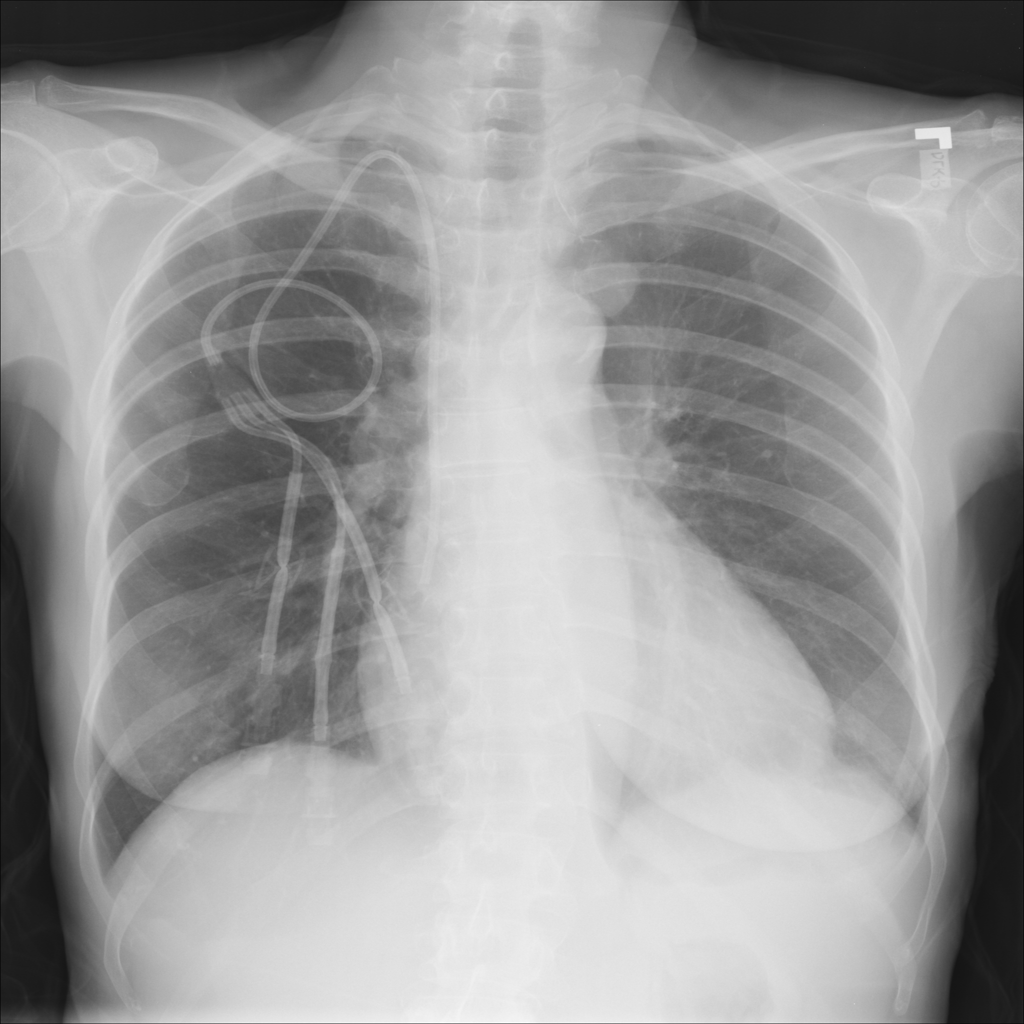

PAT-B3C3 · IMG-001Pneumonia

PAT-B3C3 · IMG-001

PA